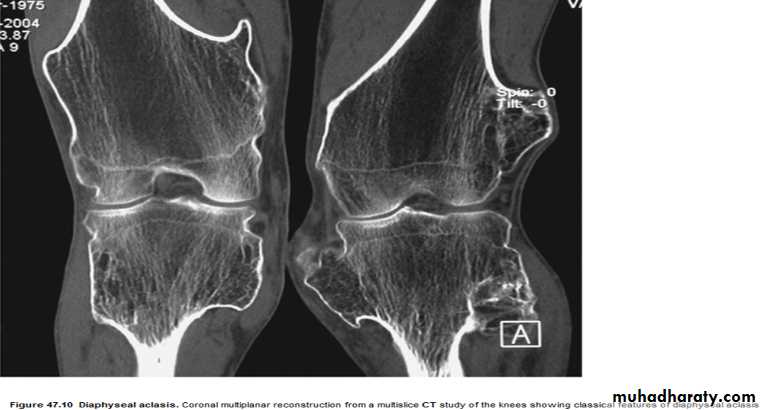

* Multiple osteochondromas are seen in Diaphyseal aclasia.

Diaphyseal aclasia.

Multiple osteochondromasEnchondroma :